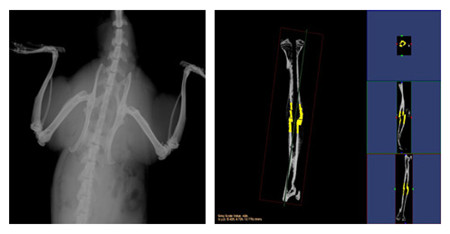

小动物CT

小动物CT服务通过采用锥形X线束,不仅能够获得真正各向同性的容积图像,提高空间分辨率,提高射线

利用率,而且在采集相同3D图像时速度远远快于扇形束CT。可以对不脱钙骨骼和动物牙齿进行microCT检测

服务,分析其内部结构和提供给您高清晰、高质量的扫描图像。活体研究对象通常为小鼠、大鼠或兔等活体小

动物,可以实现生理代谢功能的纵向研究,显著减少动物试验所需的动物数量;离体研究对象通常为离体标

本(例如骨骼、牙齿)或各种材质的样品,可分析其内部结构和力学特性。

操作简单、影像系统性能强大,确保真正的容积透视和精确定量;集成的系统结构设计使从动物放置到数据分析与

保存这一整套工作流程更高效。

结果示意图: